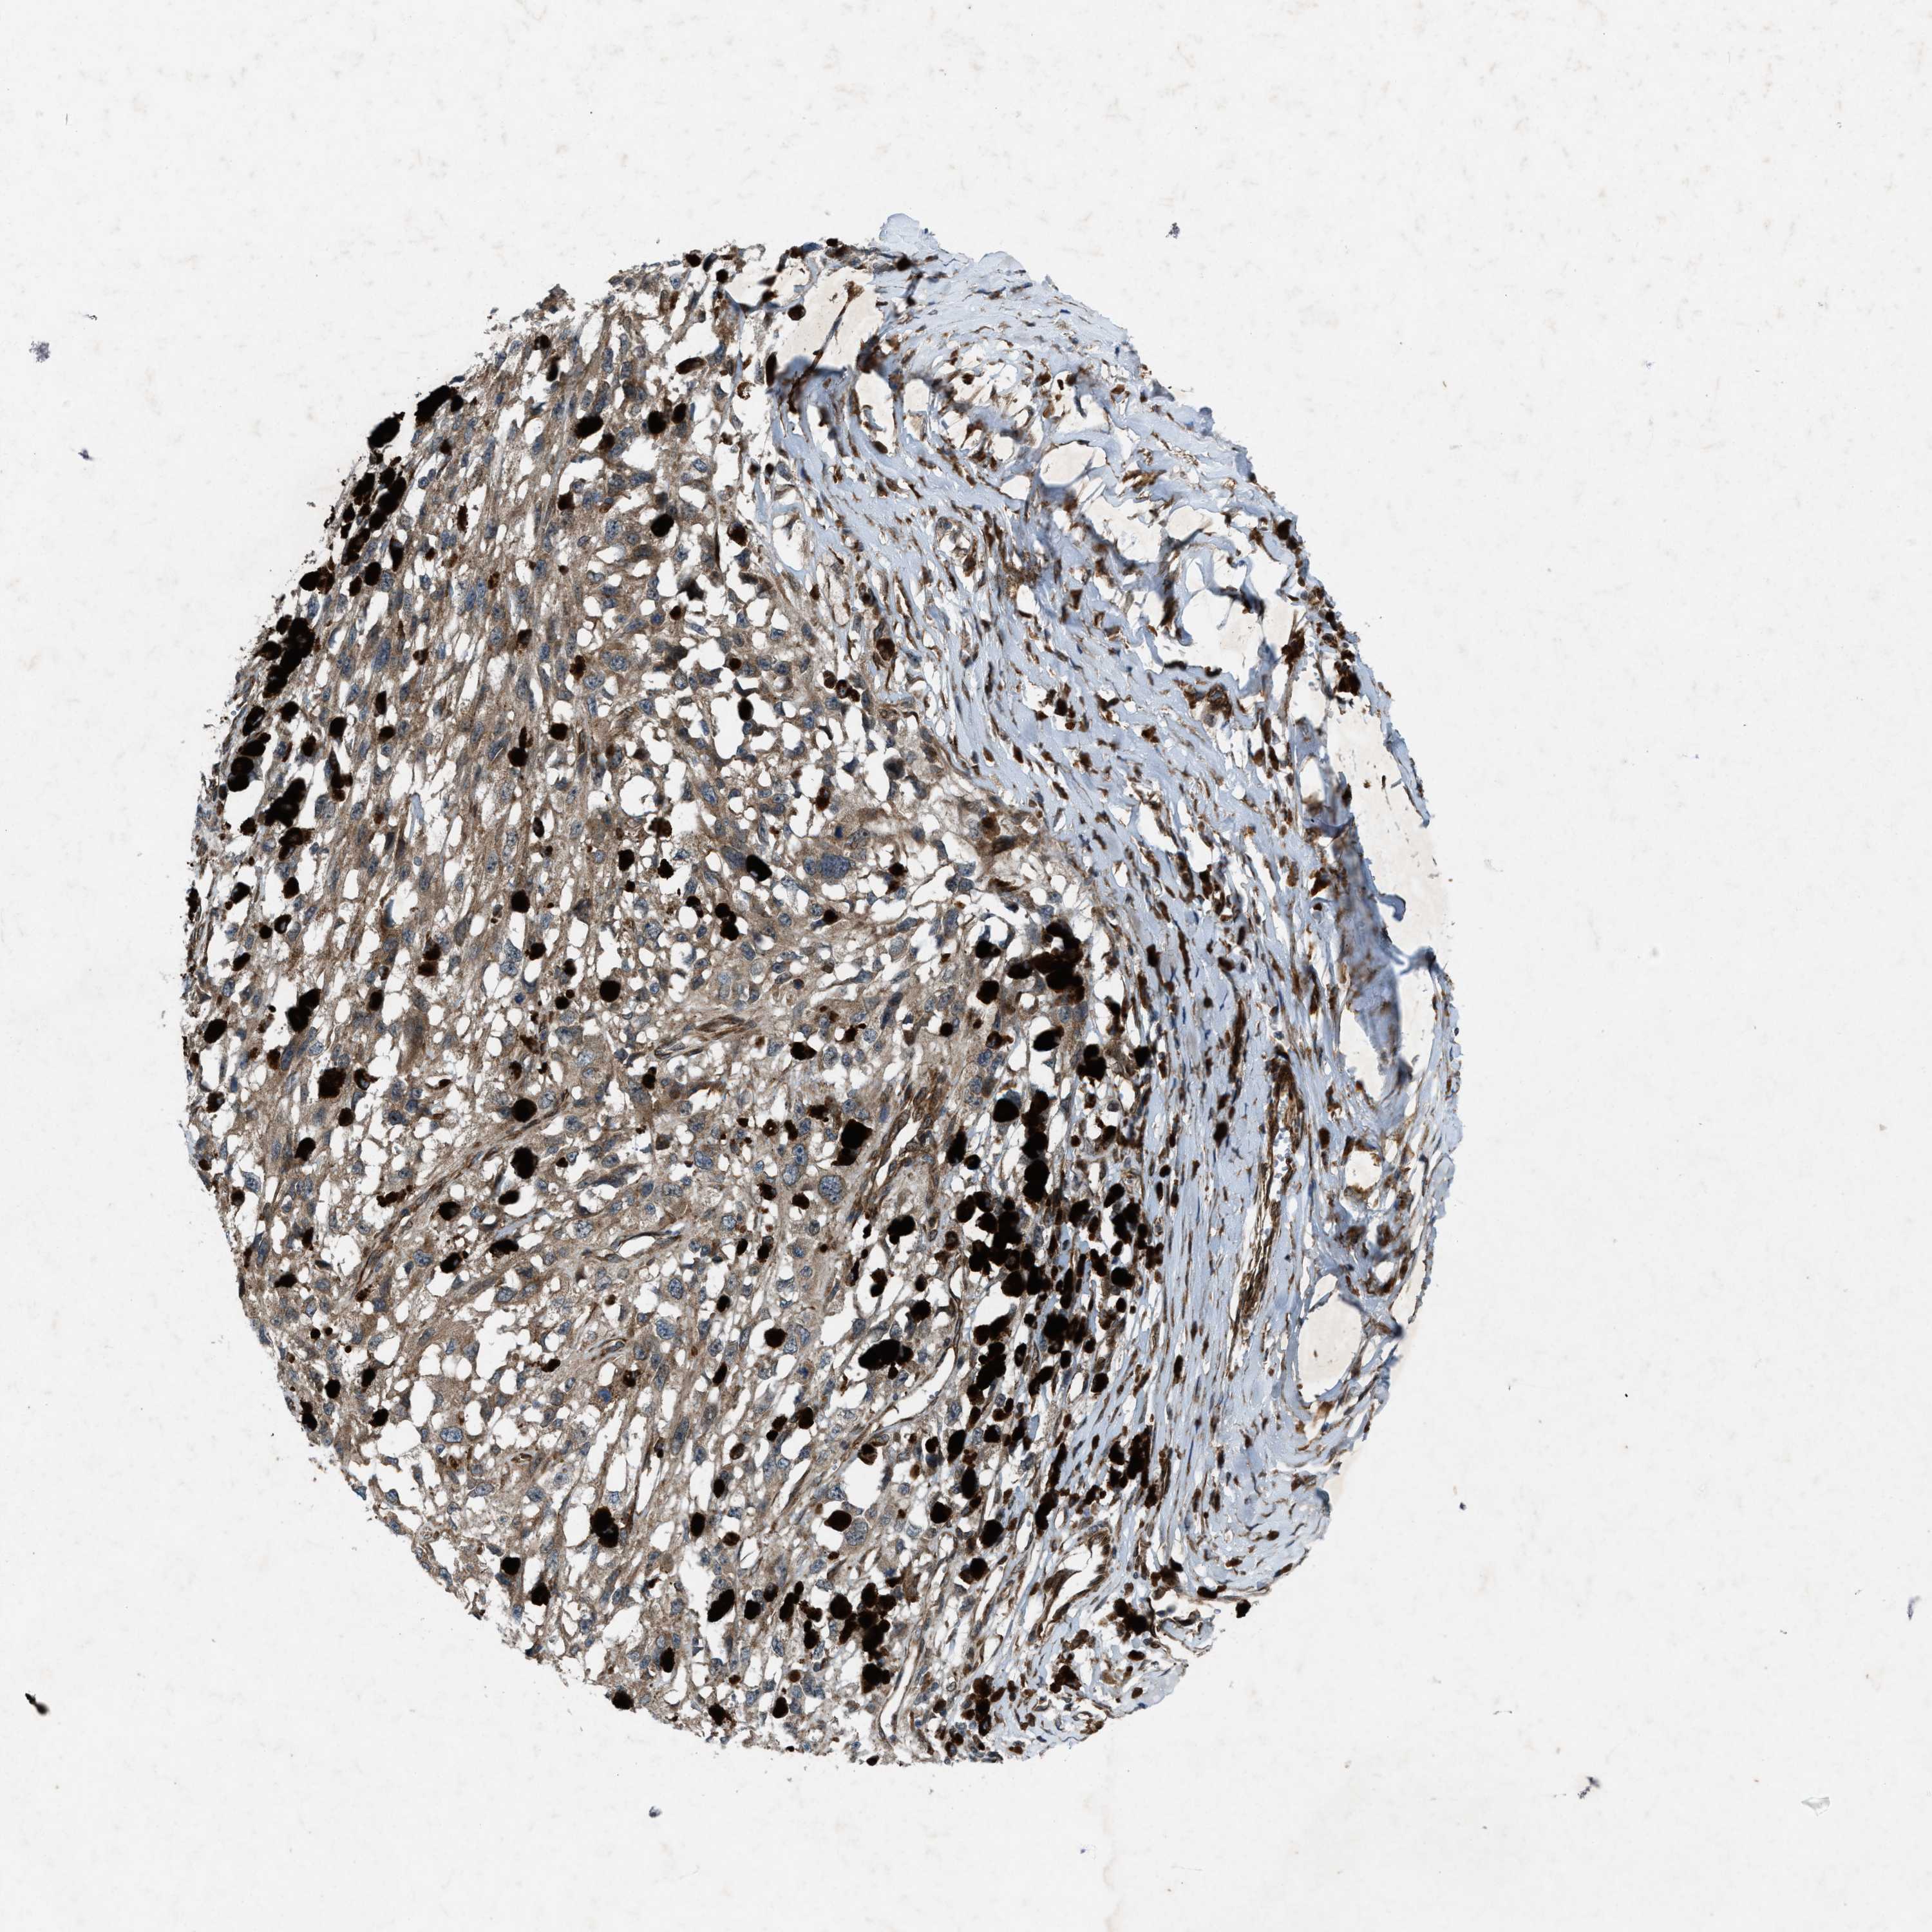

MELANOMA - Protein expressioni

A mouse-over function shows sample information and annotation data. Click on an image to view it in a full screen mode. Samples can be filtered based on level of antibody staining by selecting one or several of the following categories: high, medium, low and not detected. The assay and annotation is described here.

Note that samples used for immunohistochemistry by the Human Protein Atlas do not correspond to samples in the TCGA dataset.

Antibody stainingi

Antibody staining in the annotated cell types in the current human tissue is reported as not detected, low, medium, or high, based on conventional immunohistochemistry profiling in selected tissues. This score is based on the combination of the staining intensity and fraction of stained cells.

Each image is clickable and will lead to virtual microscopy that enables deeper exploration of all samples and also displays staining intensity scores, fraction scores and subcellular localization as well as patient and tissue information for each sample.

Antibody HPA019879

Antibody HPA020134

Antibody HPA029468

Staining

High

Medium

Low

Not detected

Intensity

Strong

Moderate

Weak

Negative

Quantity

>75%

75%-25%

<25%

None

Location

Nuclear

Cytoplasmic/membranous

Cytoplasmic/membranous,nuclear

Malignant melanoma, NOS

Malignant melanoma, Metastatic site